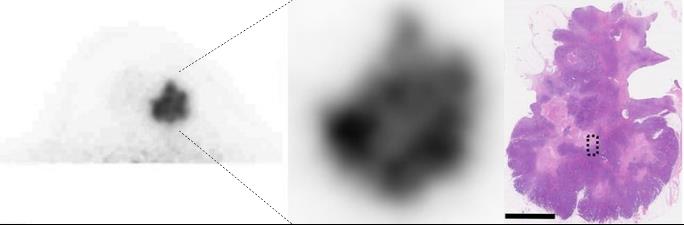

Microwave breast imaging (left) and visualization of intratumoral heterogeneity using dedicated breast PET.

We proceed with development and clinical application of new modalities of breast imaging; portable microwave breast tumor detector and ring-type dedicated breast PET.